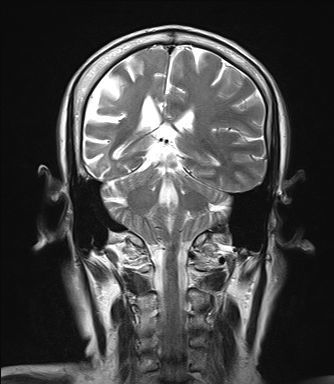

Lack of Myelination in the Anterior Limbs of the Internal Capsule Associated with Cri-du-Chat Syndrome: Case Report

H. Lee, S. You, +1 author Hyun-Hae Cho

Published 2015

Medicine

Investigative Magnetic Resonance Imaging

A 21-month-old girl with cri-du-chat syndrome in conjunction with developmental delay underwent brain magnetic resonance imaging (MRI). The MRI showed hypoplasia of the brain stem, a normal cerebellum, thinning of the corpus callosum, and a lack of myelination in both anterior limbs of the internal capsule. She also had neonatal bilateral subependymal cysts. We believe that the symmetrical lack of myelination in both anterior limbs of the internal capsule could be a diagnostic clue of cri-du-chat syndrome. LESS